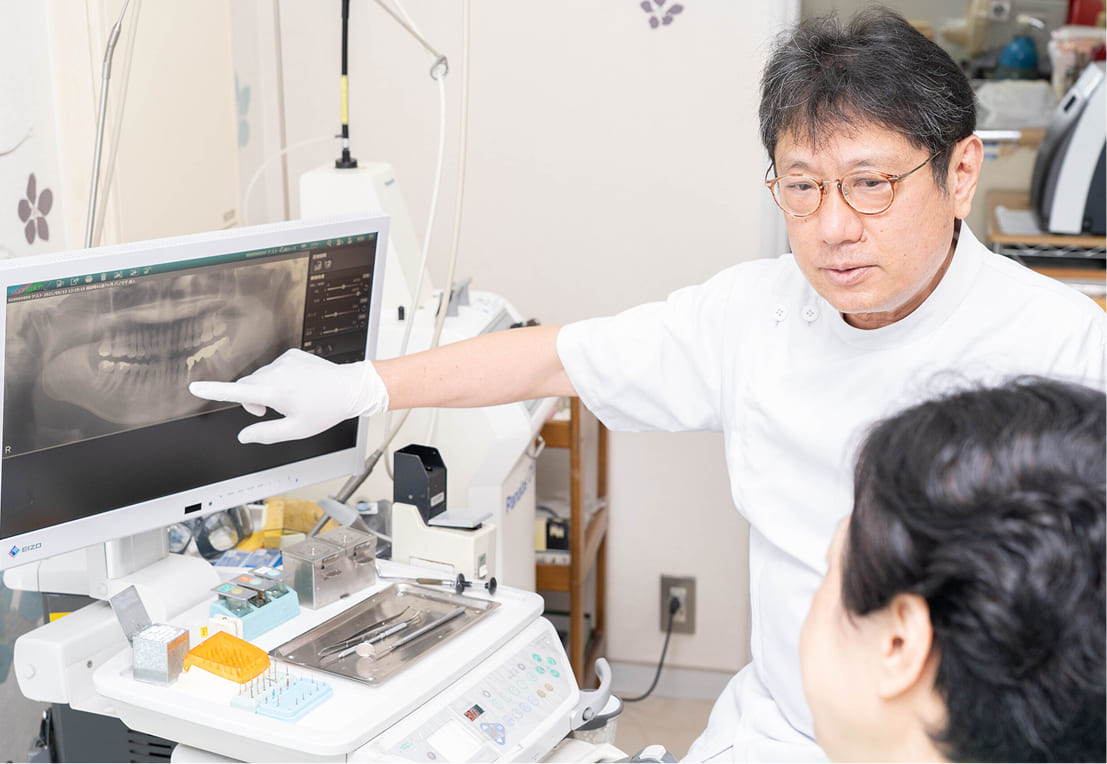

丁寧でわかりやすい説明

FEATURE01

痛みの緩和や丁寧な説明で

患者様が安心できる対応

治療に対して「痛みが怖い」「何をされているかわからない」といった不安を抱える方も少なくありません。当院では、患者様に少しでもリラックスしていただけるよう、痛みの軽減や丁寧な説明に力を入れています。電動麻酔や表面麻酔を使用し、痛みを抑えた処置を心がけるほか、iPadなどの説明ツールやカウンセリングルームを活用して、わかりやすく丁寧にご案内いたします。